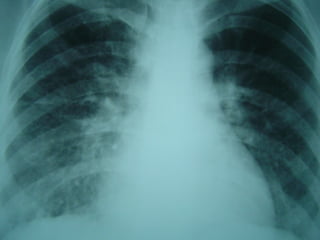

Histoplasmose Disseminada e

Pulmão